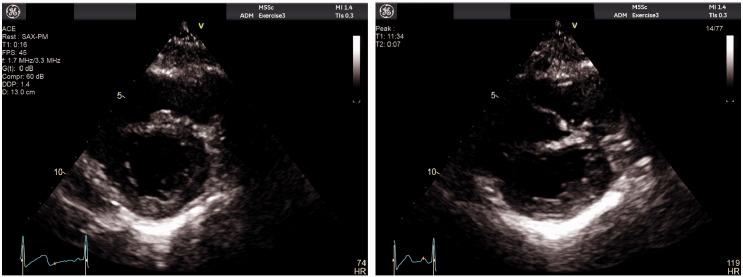

A 28-year-old aboriginal woman with known severe MS was found to be pregnant during routine health review, despite contraceptive efforts. Echocardiography demonstrated mean mitral valve (MV) gradient 14 mmHg; stress echocardiography demonstrated increased MV gradient 28-32 mmHg at peak exercise and post-exercise pulmonary artery pressure 56 + 3 mmHg with marked dynamic D-shaped septal flattening. Left ventricular systolic function remained preserved. She remained remarkably asymptomatic and underwent successful elective induction of labour at 34 weeks. Postpartum, she remained euvolaemic despite worsening MV gradients and new atrial fibrillation (AF). She subsequently underwent balloon mitral valvuloplasty with good result.

一名28岁患有严重MS的原住民女性在常规健康检查中被发现怀孕,尽管采取了避孕措施。超声心动图显示二尖瓣(MV)平均梯度为14 mmHg;负荷超声心动图显示运动峰值时MV梯度增加至28 - 32 mmHg,运动后肺动脉压为56 + 3 mmHg,伴有明显的动态D形室间隔扁平。左心室收缩功能保持正常。她一直没有明显症状,并在34周时成功进行了择期引产。产后,尽管MV梯度恶化且出现新的心房颤动(AF),但她仍保持血容量正常。随后她接受了球囊二尖瓣成形术,效果良好。